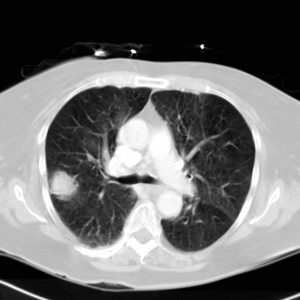

Παραδείγματα πότε μπορεί να βοηθήσει η εξέταση (ΕBUS) στη διάγνωση

Το ενδοβρογχικό υπερηχογράφημα είναι μια σχετικά νέα διαγνωστική τεχνική που μπορεί να χρησιμοποιηθεί για τη διερεύνηση βλαβών στους πνεύμονες ή στην περιοχή του θώρακα και μεταξύ των πνευμόνων. Πρόκειται για μια δύσκολη περιοχή για να απεικονιστεί και αυτό που κανονικά γίνεται με τη χρήση ενός συνδυασμού των ακτίνων Χ, αξονικής τομογραφίας και βρογχοσκόπησης, μπορεί να επιτευχθεί με το ενδοβρογχικό υπερηχογράφημα (τρεις εξετάσεις σε μία). Μέχρι πρόσφατα, προκειμένου να επιτευχθεί μια αξιόπιστη διάγνωση φυματίωσης, λεμφώματος, σαρκοείδωσης ή καρκίνου πνεύμονα χρειαζόταν παρακολούθηση του ασθενούς ή μια επεμβατική βιοψία στο χειρουργείο. Σήμερα μπορούμε να έχουμε μια βρογχοσκόπηση με ενδοβρογχικούς υπερήχους, όπου θα παρθούν στοχευμένα δείγματα ιστού από το σημείο της βλάβης και θα έχουμε αποτέλεσμα άμεσα από ταχεία βιοψία χωρίς να χάνουμε πολύτιμο χρόνο στη διάγνωση και αντιμετώπιση της ασθένειας. Πρόκειται για μια εξαιρετικά αξιόπιστη εξέταση που πραγματοποιείται ταχύτατα (30 λεπτά) και με ασφάλεια.

- Όταν η αξονική τομογραφία θώρακος αποκαλύπτει ότι ορισμένοι από τους λεμφαδένες στο κέντρο του στήθους είναι διογκωμένοι. Αυτό μπορεί να είναι ένα σημάδι του καρκίνου του πνεύμονα ή σαρκοείδωσης, φυματίωσης ή λεμφώματος.